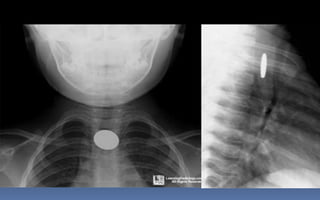

DENSIDADES BÁSICAS:

1. METALICA: BLANCO BRILLANTE

2. CALCICA: BLANCO CLARO

3. AGUA: GRIS CLARO

4. GRASA: GRIS OSCURO

5. AIRE: NEGRO